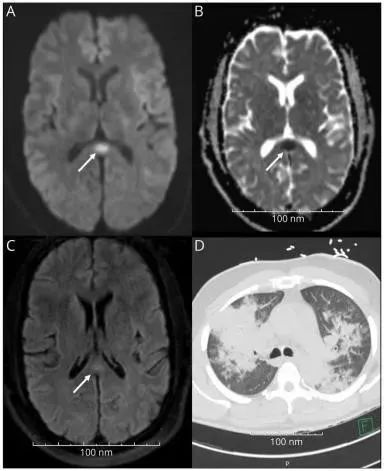

动脉血气显示继发于乳酸酸中毒的阴离子间隙酸中毒;白细胞15.7;肝肾功能障碍。胸部CT显示双侧实变(图);快速COVID-19测试呈阴性。头颅MRI平扫显示胼胝体压部有一小的弥散受限病灶(图)-与细胞毒性病变一致。鉴于该部位血管性原因可能性不大,需进一步筛查感染性病因,包括HIV、军团菌、细小病毒B19、CMV、EBV,以及A型和B型流感腺病毒、副流感和等呼吸道全套检测。

图 头颅MRI大脑和胸部CT。(A)MRI弥散加权序列可见胼胝体压部高信号病灶。(B)ADC序列显示胼胝体压部低密度信号。(C)FLAIR显示胼胝体压部高信号病灶。(D)胸部显示双肺实变。